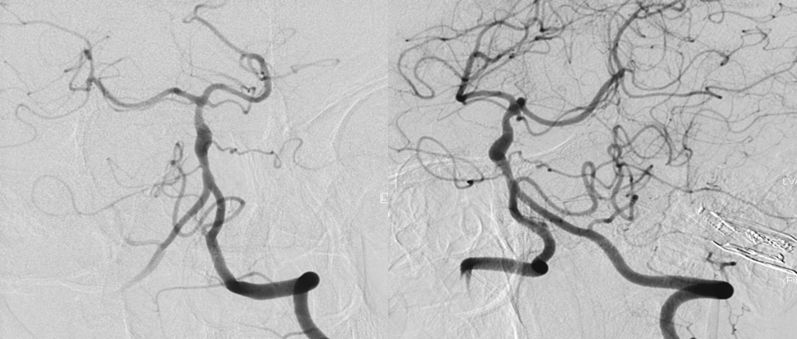

当地医院DSA:基底动脉中上段夹层动脉瘤(2019-09-10)(图3)。

图3

本院DSA:基底动脉巨大夹层动脉瘤,双侧后交通动脉未见明显开放(图6)。

图6

2、头部核磁共振显示:脑干占位性病变,边界较清晰,较大层面大小约35 mmx25 mm。MRA显示:基底动脉夹层动脉瘤。DSA显示,基底动脉巨大夹层动脉瘤,最大长径为:10.8 mm,最大短径为3.2 mm。根据患者症状及影像学诊断,基底动脉巨大夹层动脉瘤进行性增大压迫脑干,不排除脑干水肿可能,亟待手术治疗。

3、由于双侧后交通动脉未见明显开放,为保证脑干血供,手术必须确保载瘤动脉通。动脉瘤累及左侧AICA,基底动脉穿支丰富,位置深在,而且动脉瘤为夹层动脉瘤开颅手术治疗困难,且风险极高。回顾文献及本中心治疗经验,此类动脉瘤血流导向装置疗效较好,经科内讨论后决定运用Tubridge血流导向装置治疗。